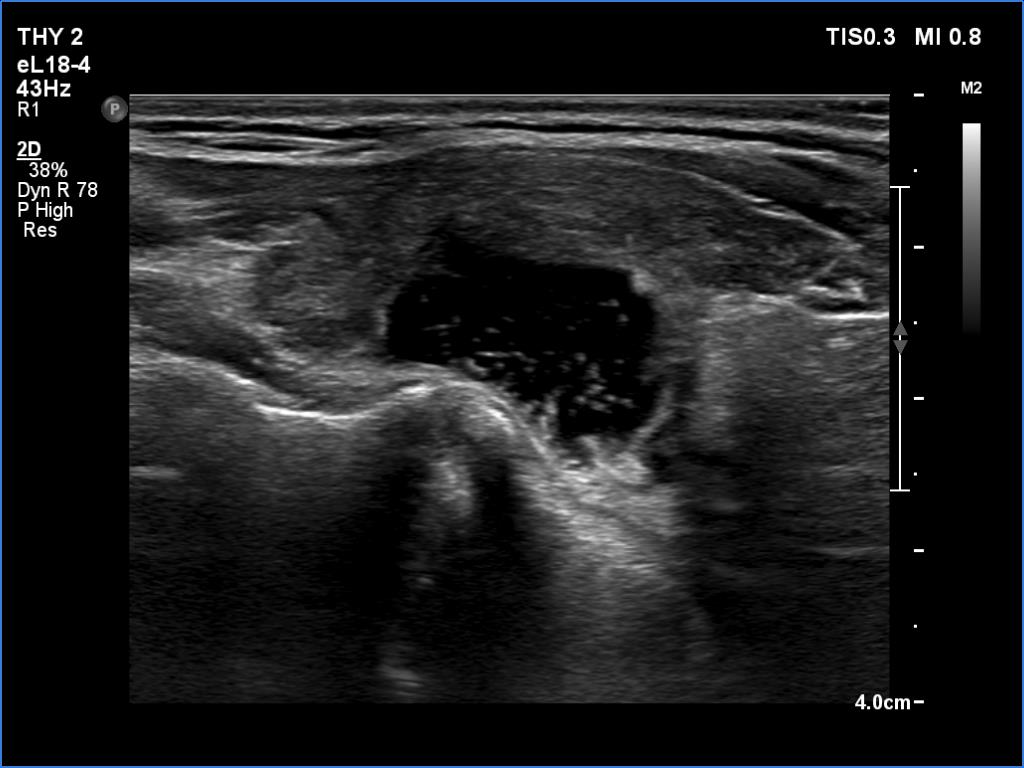

Ultrasonography. The thyroid was hypoechoic and presented several more hypoechoic and echonormal islets corresponding to the underlying thyroiditis. There was a mixed, dominantly cystic mass dorsal to the lower two-third of the right lobe. The lesion has echonormal solid part and showed intracystic echogenic figures.